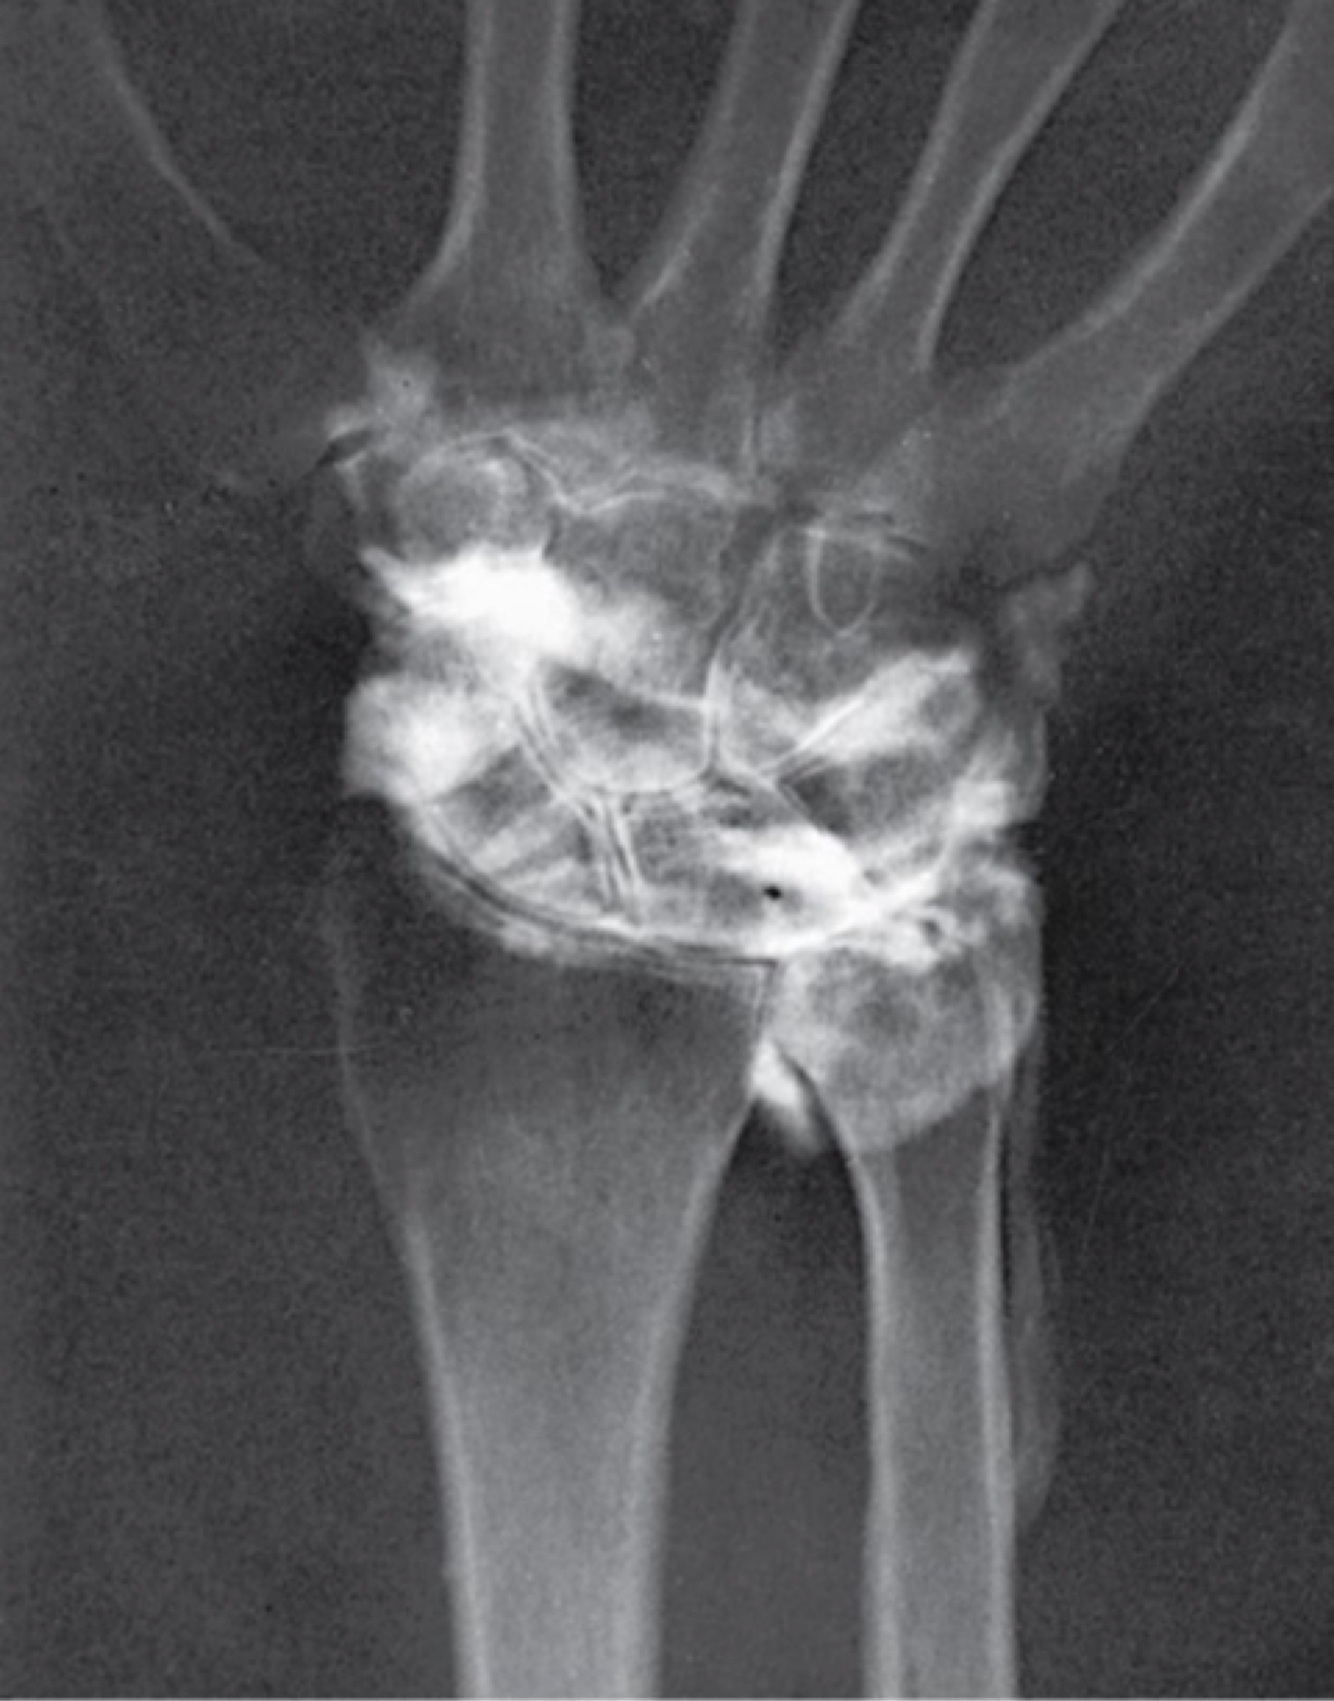

Wrist Arthrogram